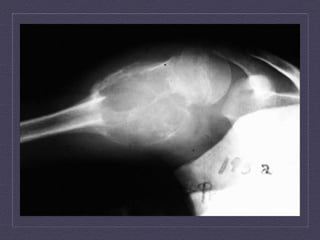

AP  and  lateral  views  of  the  right  hip  demonstra:ng  a  ly:c  lesion   with  peripheral  sclerosis  of  the  right  proximal  femur